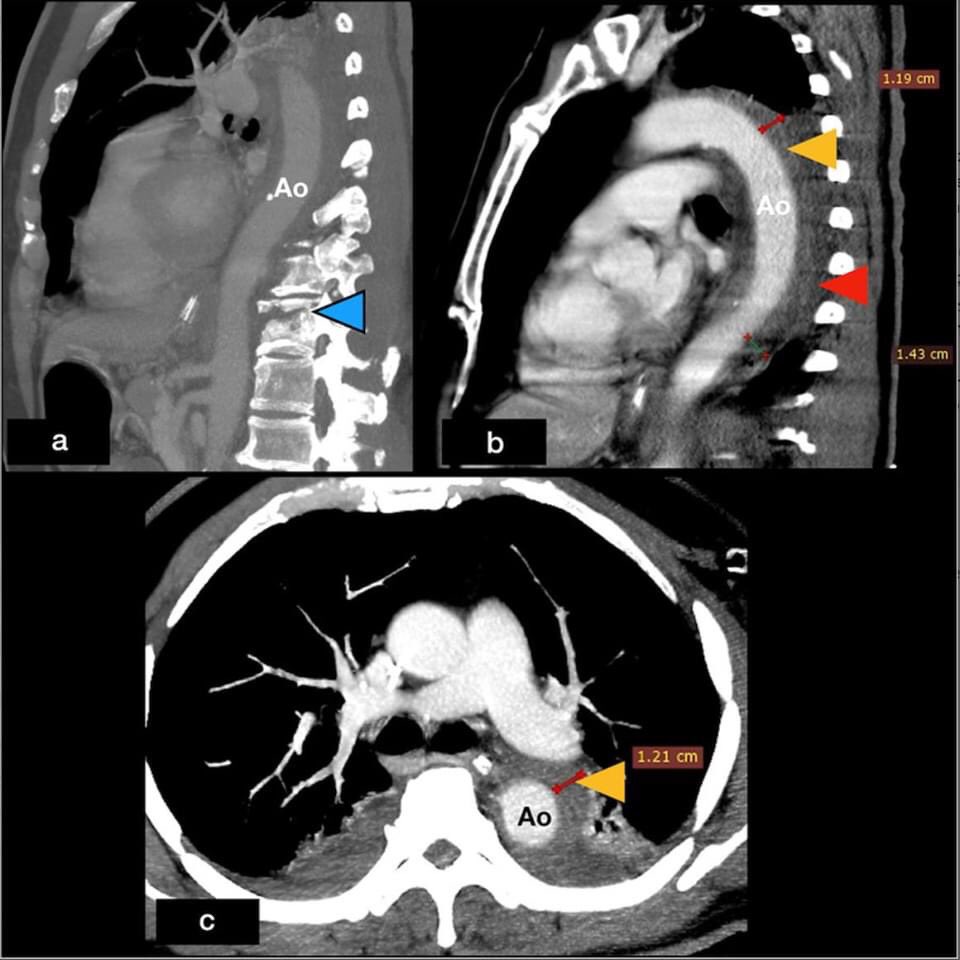

"Hypotensive traumatic paraplegic " .Sharing our images/video and the role of Emergency Department TEE in diagnosis of blunt traumatic aortic injury. #JACEPOpen

https://t.co/gUxgGDG0hd

The use of TEE during resuscitation continues to expand in acute care settings: Transesophageal Echocardiography at the Golden Hour: Identification of Blunt Traumatic Aortic Injuries in the Emergency Department https://t.co/n2z13OWseJ